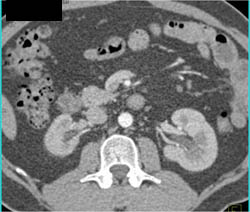

Retroperitoneal Fibrosis